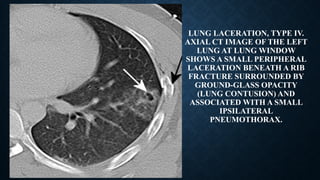

Pulmonary laceration types 1–3. (A)

axial CT image in a 27-year-old man

shows three centrally located

intraparenchymal lacerations type 1,

compression rupture (pneumatocele

and hematopneumatocele). The

surrounding ground-glass

attenuation, reflecting contusions and

moderate pneumothorax.

(B) axial CT image in a 33-year-old

man shows a paravertebral air-filled

laceration (pneumatocele) type 2,

compression shear laceration

(pneumatocele).

(C) axial CT image in a 24-year-old

man shows a peripheral air-filled

laceration (pneumatocele) subjacent

to the thoracic ribs, type 3, rib

penetration tear.